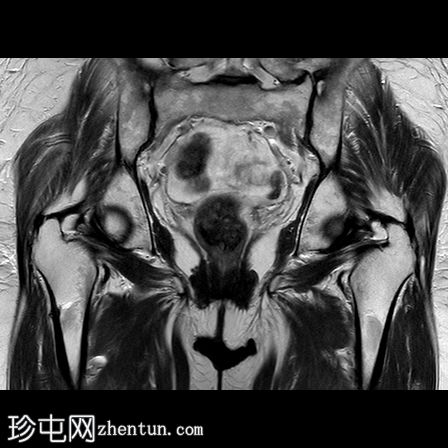

X光片

右股骨干近端1/3可见外侧皮质轻微骨膜增厚。内侧皮质正常。除关节周围软组织钙化外,髋关节未见异常。